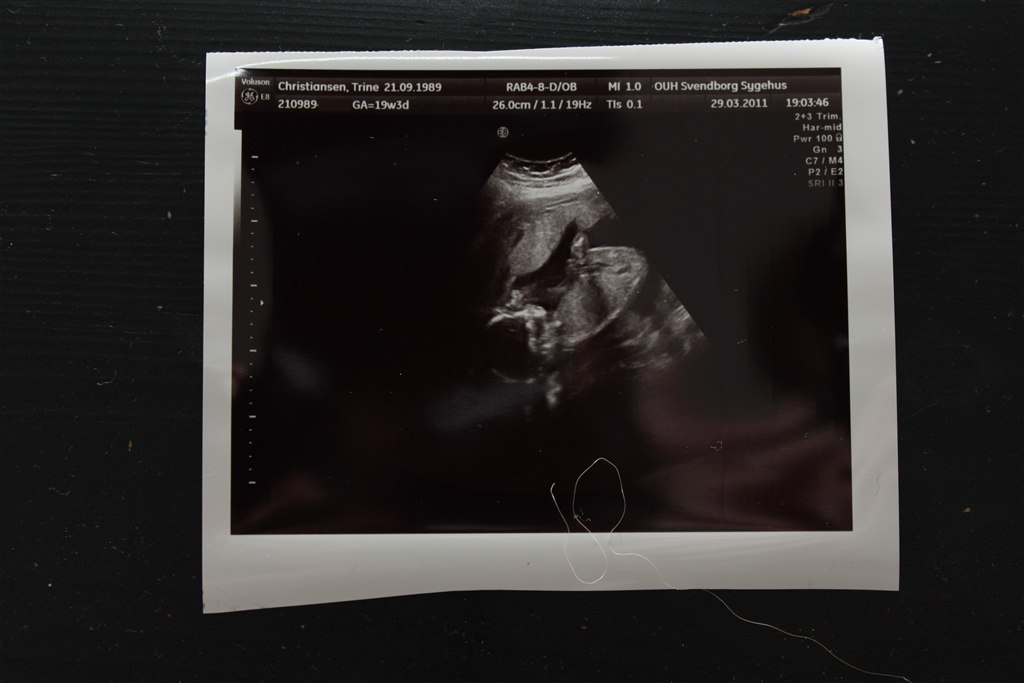

Et lille billede af vores elskede Mini T

Vedhæftede fotos (klik for at se i fuld størrelse)

og så startede hun ellers med at scanne.. og alt ting var Bare SÅÅ flot, målene på hovedet, maven osv var bare så flotte.. Hjerne, hjerte, nyre og blæren var også super flotte.  Så det kunne jo ikke blive bedre.. min lille mini T har det bare SÅÅ godt..

Trine - Uge 19+3